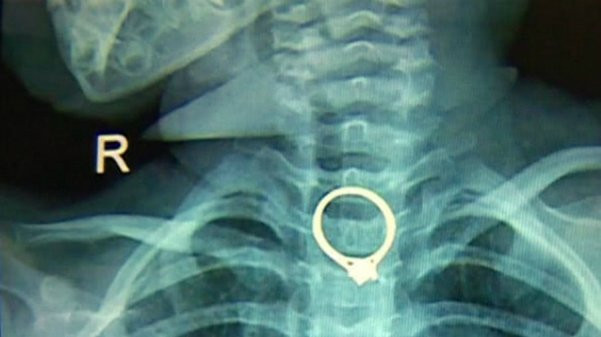

Chiếc nhẫn kim cương mắc kẹt trong cổ họng bé gái.

10 phút sau, tiếng kêu thất thanh của con gái khiến chị tỉnh giấc. Deng bàng hoàng khi biết con gái nuốt phải chiếc nhẫn. Bà mẹ trẻ ngay lập tức đưa con gái tới bệnh viện, các bác sĩ sau đó xác nhận chiếc nhẫn bị mắc kẹt trong thực quản của cô bé.

“Chiếc nhẫn có khá nhiều cạnh sắc. Nếu cô bé nuốt sâu hơn, chiếc nhẫn có thể xuống tới dạ dày và gây ra hậu quả nghiêm trọng”, bác sĩ Chen Gang tại bệnh viện cho hay.